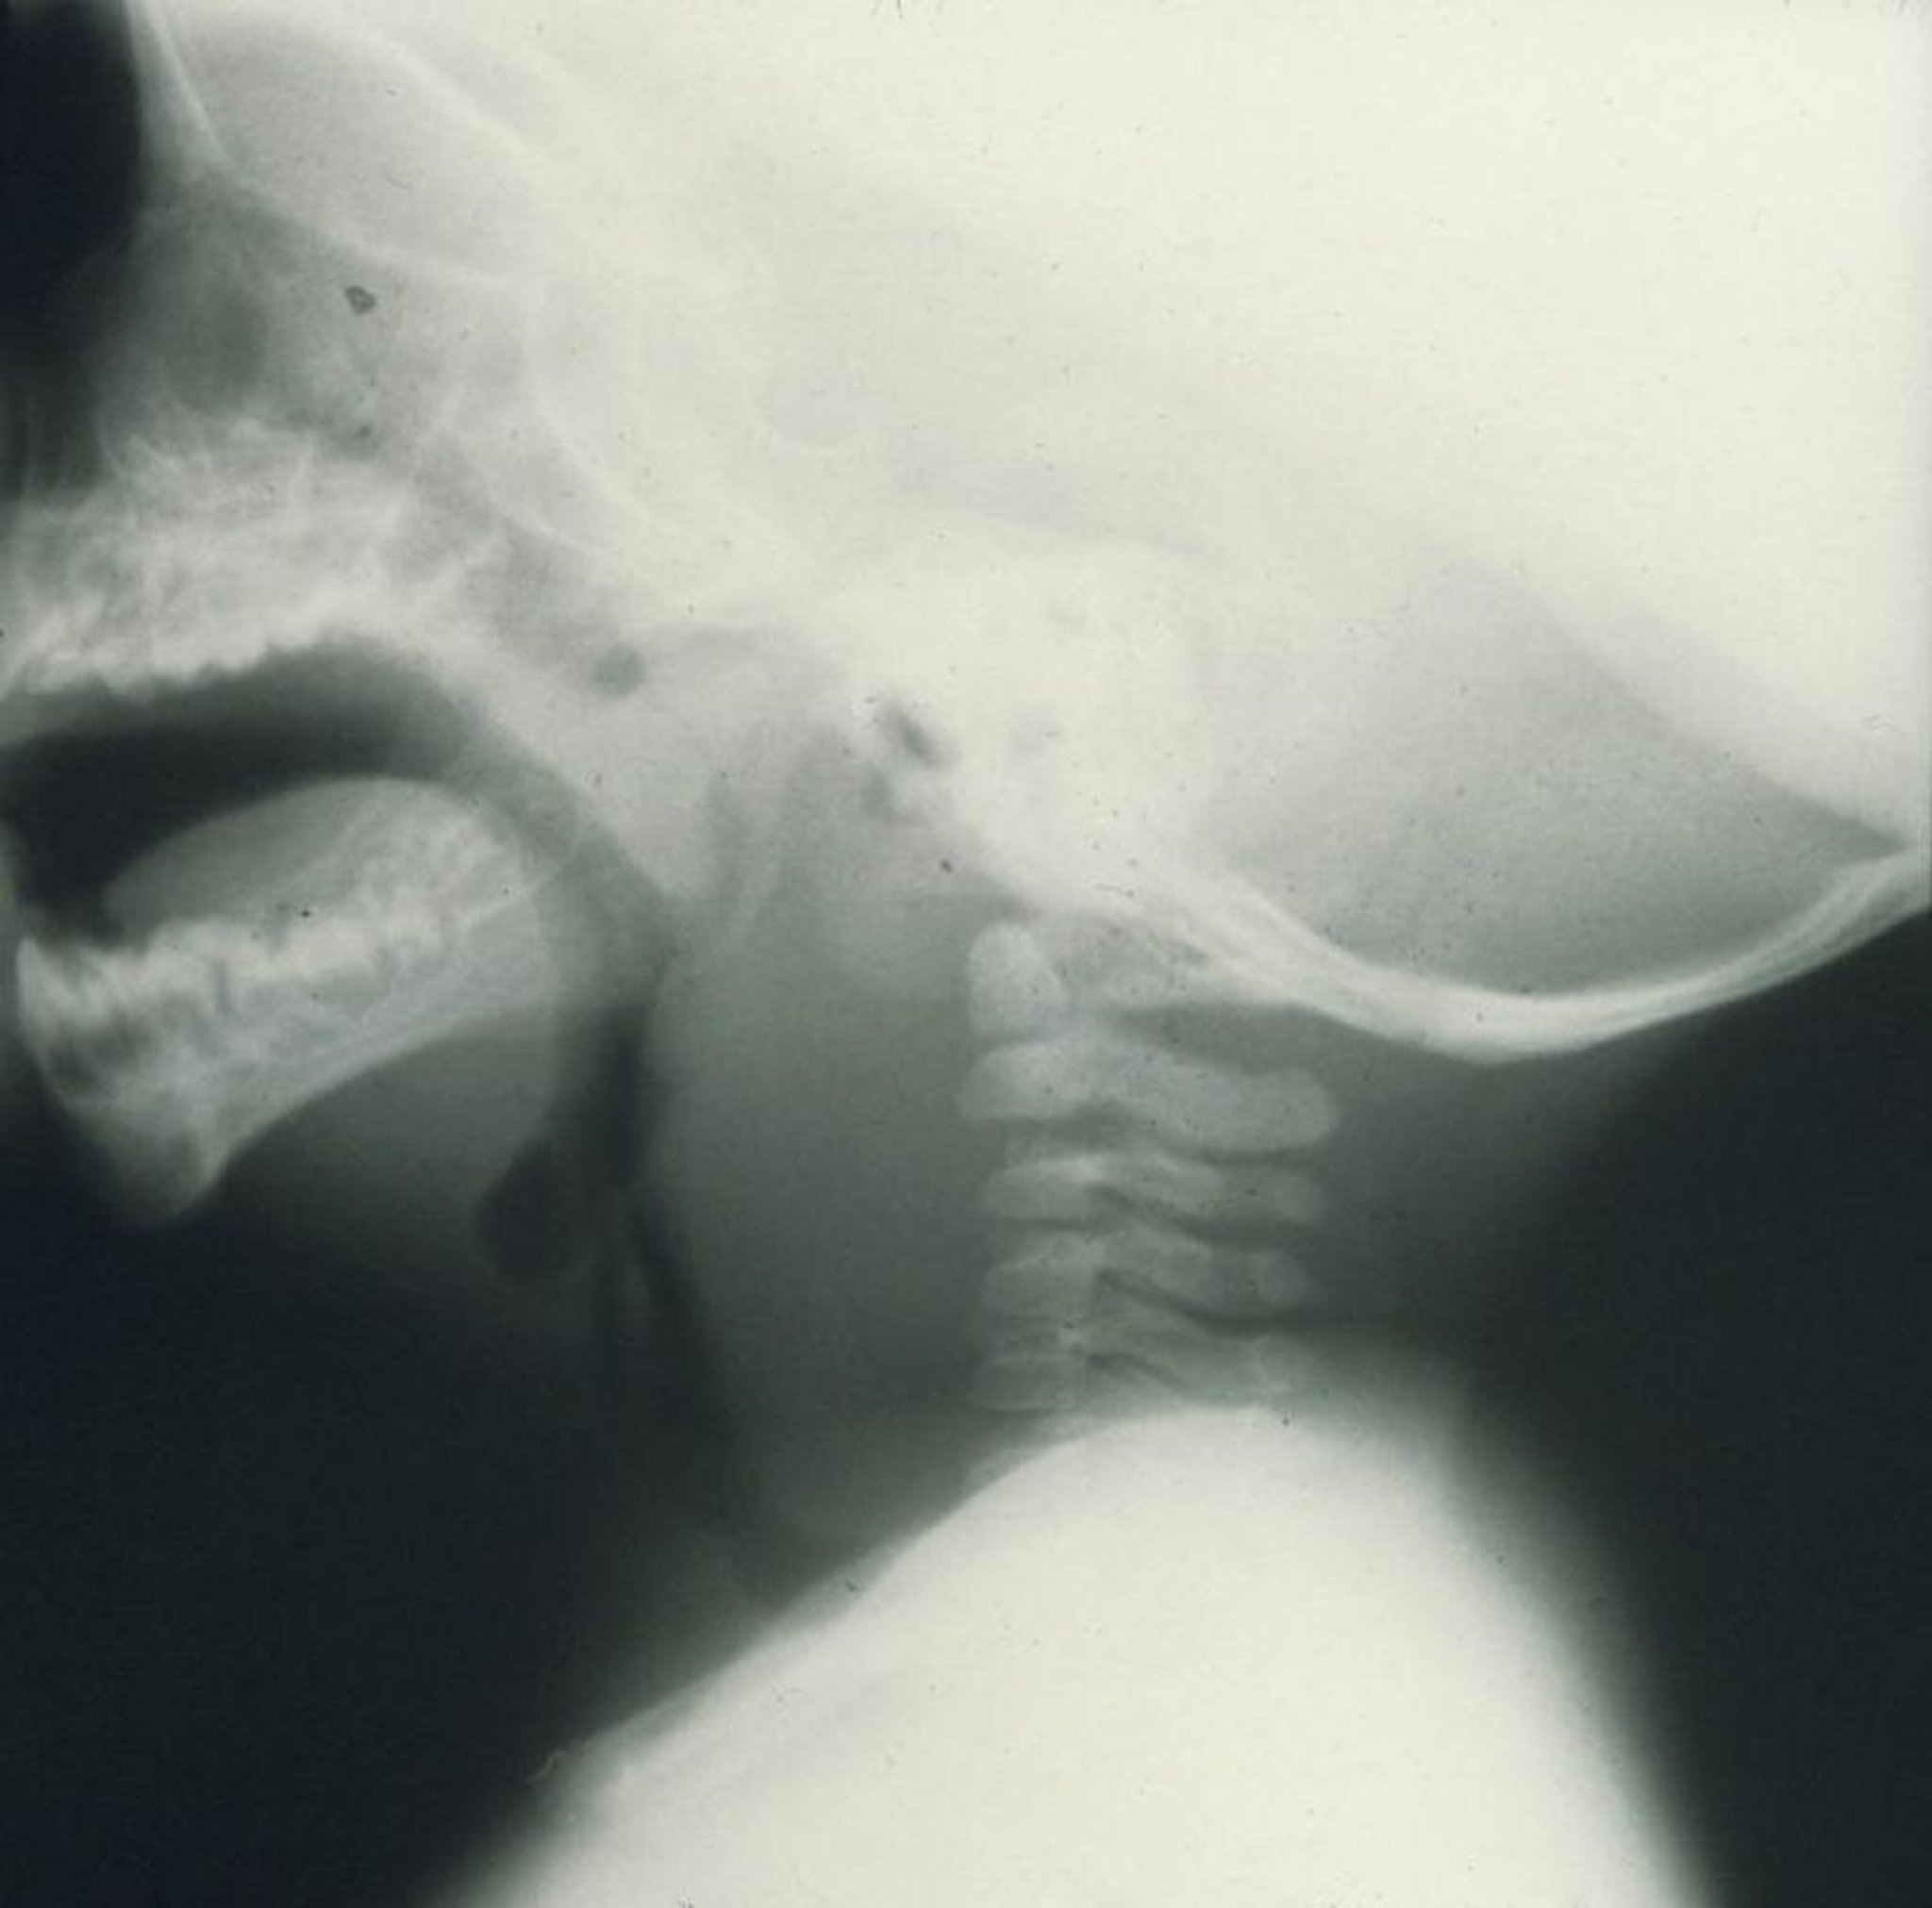

Abcès rétropharyngé

Cette radiographie de profil d'un enfant montre un gonflement marqué en avant des vertèbres cervicales causé par un abcès rétropharyngé.

Image provided by Clarence T. Sasaki, MD.